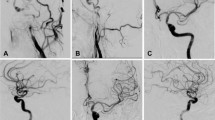

Surgical recanalization was performed in all patients (Figs. 2, 3), with successful recanalization in 119 (99.2%) patients in the proximal plaque group and 39 (92.9%) in the distal plaque group, with no significant (P = 0.52) difference between the two groups. One (0.8%) patient was not successfully recanalized in the proximal group and 3 (7.1%) in the distal group. The total successful recanalization rate was 97.5% (158/162) with a failure rate of 2.5% (4/162).

Distal atherosclerotic plaques causing long-segment occlusion of the internal carotid artery (ICA) treated with hybrid surgery in a patient in their 40 s with dizziness and left limb weakness. (A) Magnetic resonance imaging (MRI) showed multiple acute infarction lesions in the right hemisphere. (B–E) The time-to-peak (B) and mean transit time (C) were prolonged, and the cerebral blood volume (D) and cerebral blood flow (E) were decreased. (F) Computed tomography angiography revealed occlusion of the right ICA. (G) Digital subtraction angiography demonstrated occlusion of the right ICA. (H,I) Arteriotomy of the right ICA was performed for use of a Forgarty balloon to remove the atherosclerotic plaque (H), and the thrombus was approximately 7 cm long (I). (J,K) After plaque removal and recanalization of the ICA, a stenosis of the ICA ophthalmic segment was treated with balloon dilation, and smooth blood flow was resumed in the right ICA even though a slight stenosis remained at the ICA ophthalmic segment.